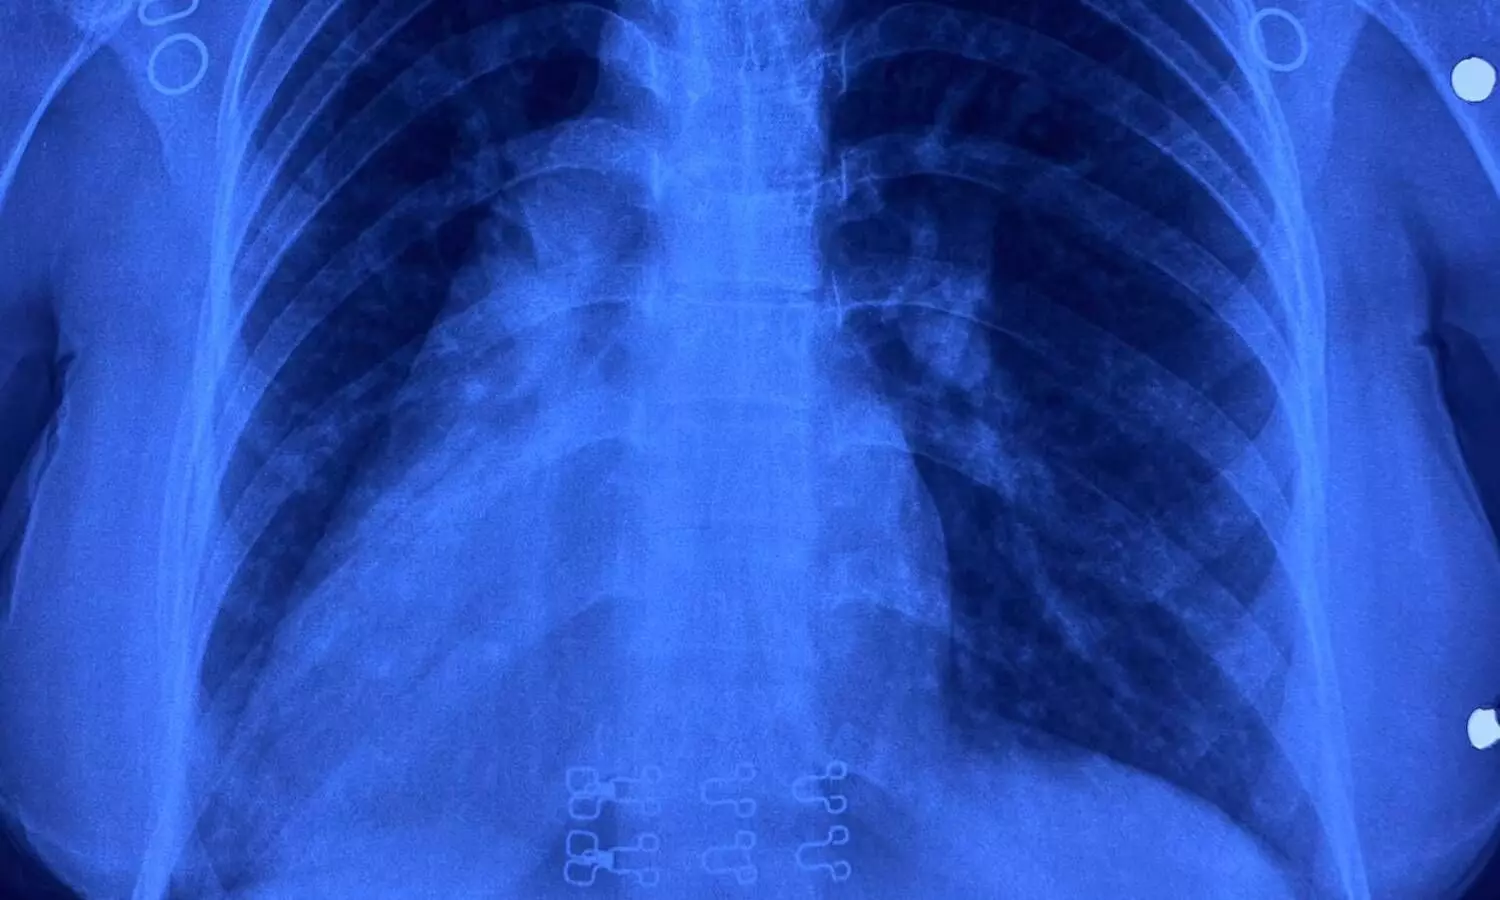

31 वर्षीय रामबाई एक जन्मजात हार्ट की बीमारी (Congenital Heart Disease) से पीड़ित थीं. उनकी स्थिति बेहद दुर्लभ थी. उनका दिल दाईं ओर (Dextrocardia) था. लिवर बाईं ओर, तिल्ली (Spleen) दाईं ओर और पेट भी दाईं ओर था. उन्हें 'पार्शियल एट्रियोवेंट्रिकुलर कैनाल डिफेक्ट' था, जिसमें दिल के बीच के हिस्सों में छेद होता है.

आमतौर पर ऐसी जटिल सर्जरी के लिए सीने की हड्डी (Chest Bone) को काटना पड़ता है, लेकिन डॉ. नरेंद्र सिंह झाझरिया और उनकी टीम ने इसे मात्र 4 सेंटीमीटर के छोटे से कॉस्मेटिक कट (Left Inframmary Incision) के जरिए इस काम को सफलतापूर्वक किया.

मरीज के अपने ही पेरीकार्डियम (दिल की झिल्ली) से पैच बनाकर छेद को भरा गया. दिल के वाल्व और इलेक्ट्रिक कंडक्शन बंडल को नुकसान पहुंचाए बिना इतनी बारीकी से टांके लगाना उच्च स्तर के कौशल की मांग करता है. डॉ. जसविंदर कौर कोहली और उनकी टीम ने इस जटिल प्रक्रिया के दौरान मरीज की मॉनिटरिंग और एनेस्थीसिया का बखूबी मैनेज किया.